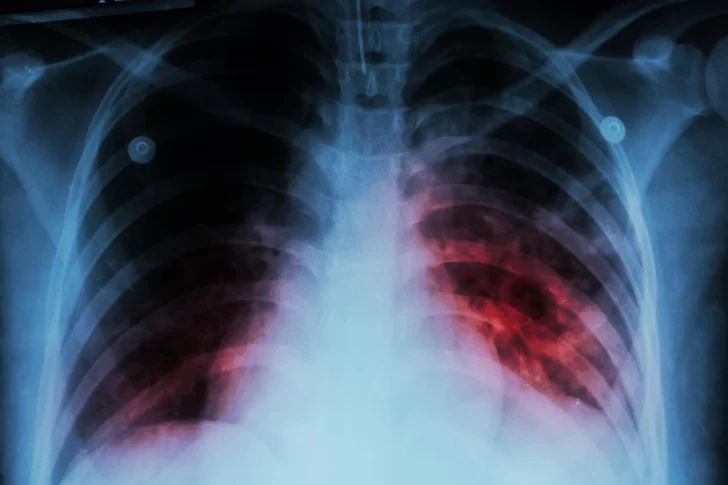

Se trata de una enfermedad infecciosa que afecta a los pulmones y que es causada por una bacteria (Mycobacterium tuberculosis) que se transmite de una persona a otra a través de las gotitas de aerosol que permanecen en el aire tras haber sido expulsadas por personas con enfermedad pulmonar activa. Se estima que una cuarta parte de la población mundial está infectada por el bacilo de la tuberculosis, pero (aún) no ha enfermado ni pueden transmitir la infección. Este grupo de personas infectadas de forma latente tiene un riesgo de enfermar de tuberculosis a lo largo de su vida de entre el 5% y el 10%.

Los principales síntomas de esta enfermedad son: tos (a veces con esputo que puede ser sanguinolento), dolor torácico, debilidad, pérdida de peso, fiebre y sudoración nocturna. Es importante considerar que los síntomas dependen de la magnitud del compromiso, del tiempo de evolución del cuadro, de la edad y del estado inmunológico del paciente. Estos signos, a veces solapados durante muchos meses, ocasionan retrasos en la búsqueda de la atención médica y en la detección. Muchas veces, el cuadro se puede confundir con otras enfermedades y cuanto mayor es la demora en el diagnóstico de la enfermedad, hay un mayor riesgo de contagio a otras personas.